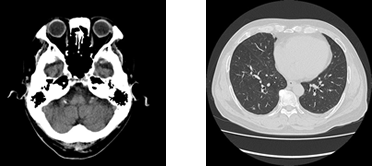

CT検査

CTとは、ComputedTomography(コンピューター断層撮影)の略語です。X線を利用して、体内の情報を集め計算により人体の横断像 (輪切り)を撮影することが出来ます。検査時間は、検査の内容や部位によって異なりますが約5~20分程度の短時間ですみます。また、造影剤を使用することにより、あらゆる血管(脳・胸部・腹部・上下肢血管)や腫瘍などの撮影が可能となります。

さらに、CTで収集したデータを用い画像処理ワークステーションを使用して様々な方向の断層像や、骨や血管などの3D画像を作成することも可能です。(下記の心臓CT検査やCTコロノグラフィー検査もワークステーション処理によるものです)

2019年4月より当院は最新のCT装置を導入し、従来の装置と合せ2台運用とすることで救急医療にも更に迅速に・いつでも対応できるよう体制を整えています。

キャノンメディカルシステムズ(株)(旧:東芝メディカル)の80列マルチスライスCTスキャナでAquilion Prime SPという装置です。